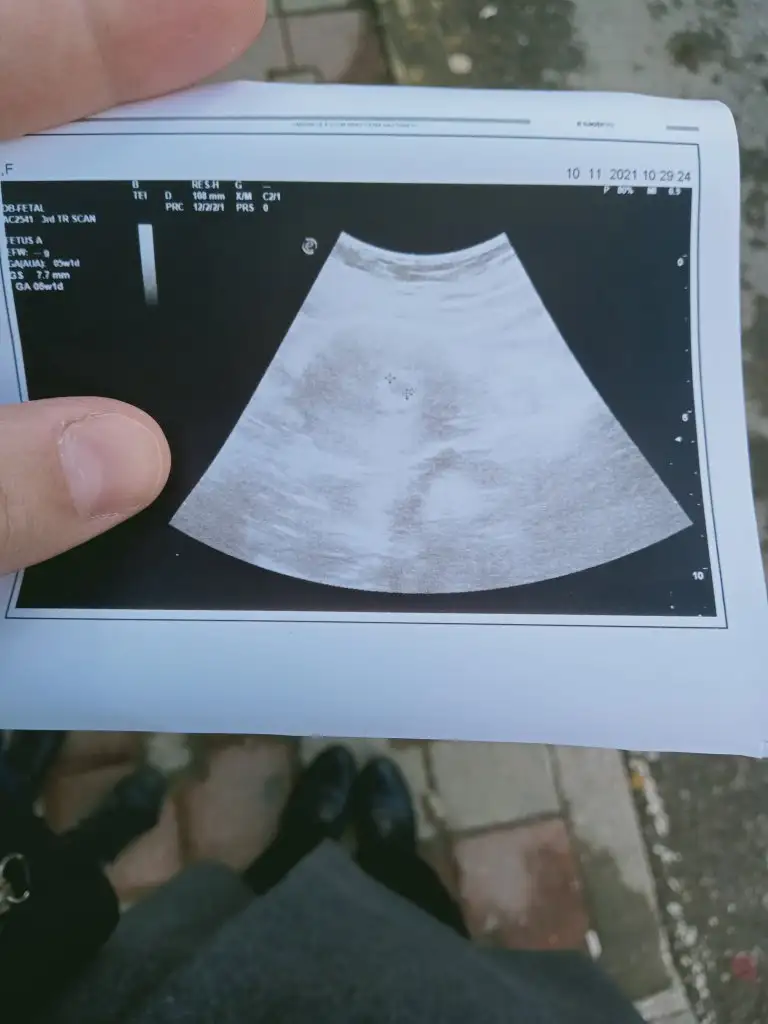

Canımm gözünaydnBu sefer özelde bile bulamayacagım 4.4 luk bir dr geldm karnımdakıyle ilgilenmesı ayrı kucuk oglumla ilgilenmesi ayrı guzeldiortam yok ya ıysını buluyorum ya kotusunu bu arada kesecümüü gördüm rahtladım doktor kanama kist vb yok haftasıyla hatta günü gününe uyumlu kesen dedi ilerleyen haftalrda kan tahlili isteyecgni ona gore hareket edecegmzii soyledi simdilik hersey yolunda hamdolsun